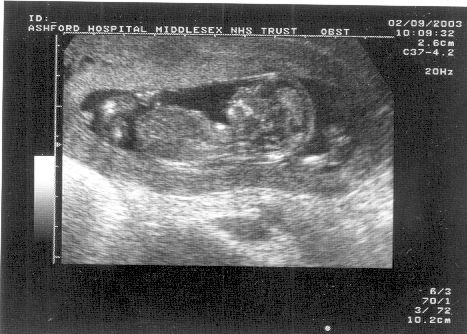

Yup, on 2nd september, Estelle

and Nick went to Ashford Hospital

for their 12 week scan,

expecting to later surprise everyone at work by bringing in an

ultrasound and announcing that we were going to be parents

again.

We weren't expecting quite such a surprise ourselves! TWINS!

Pics:

One baby:

Another baby:

Both together:

Identical? Apparrently not. If you look closely at the 3rd

picture, you can see they're in seperate sacks. That means they're

ALMOST certainly fraternal (non-identical) twins.